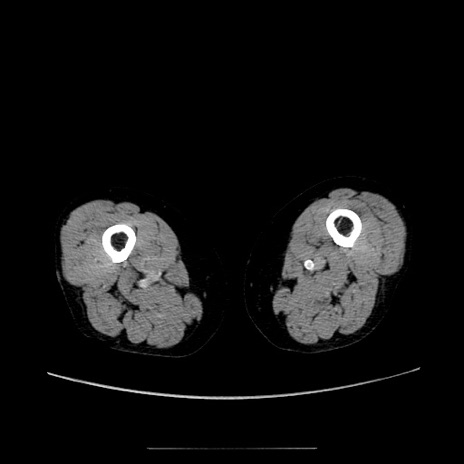

症例5(横断像)

【症例】70歳代女性

【主訴】お腹が張る

【現病歴】1週間くらい前から腹部膨満の自覚あり。昨日夜から増悪したため、本日救急外来受診。

【身体所見】意識清明、BT 36.5℃、BP 165/106mmHg、HR 80bpm、SpO2 98%、腹部:膨満、軟、自発痛・圧痛なし、触診にて不快感あり、腸蠕動音:減弱

【データ】WBC 12600、CRP 1.04